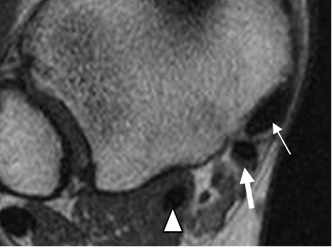

Fig 17. Ligamento calcaneoescafoideo.

A: RM axial en T1 y B: RM sagital en T2. Ligamento hipointenso normal, entre el escafoides y el calcáneo.